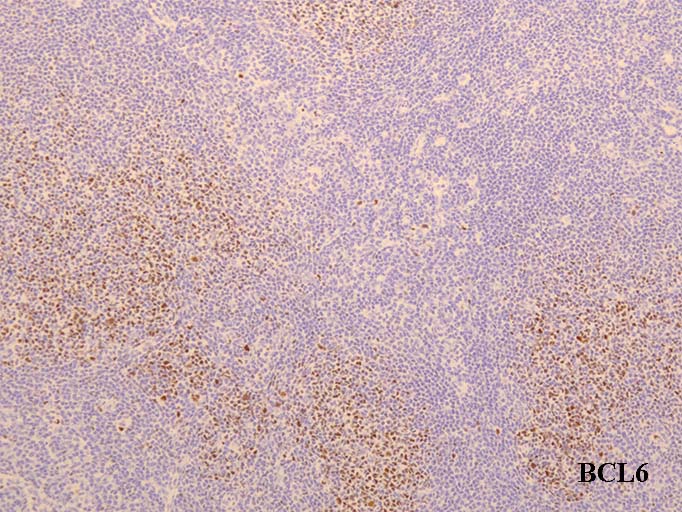

GC01.jpg

リンパ節の皮質cortexは, primary follicle(一次濾胞)とsecondary follicle(二次濾胞; 右図)から構成される.

bcl-2陽性. CD10, bcl-6は陰性. bcl-2陽性の一次濾胞をFLと間違えないよう注意.

secondary follicle;

胚中心(germinal center: GC)とmantle zoneをもつ.

mantle zoneはprimary follicle構成細胞と同じB細胞からなる. mantle zoneには厚い薄いがみられ, 薄いときはmantle zoneがないように見え, 子供のリンパ節に多い.

germinal center(GC)は, B細胞, T細胞, 抗原提示細胞, tindible-body macrophageが混在して構成されている. B細胞が優位に多く, small/ large cleaved cell(centrocytes)とlarge non-cleaved cells(centroblasts)が認められる。

正常胚中心のcentrocyte, centroblastsはbcl-2陰性であり, CD10, bcl-6が陽性となる. surface Igは低レベルであるが細胞質に通常 μ重鎖タイプ(IgM)Igが認められる.

T細胞はCD4+/ CD8-のhelper/inducer cellsであり, follicular (helper)T-cell:Tfhとよばれる. PD-1+, CXCL13+, CD57+.

CD21+, CD35+, CD23+とclusterin+ CD23はときに陰性のことがあるので注意.

高度に活性化された胚中心では, centrocyteとT細胞から構成される light zone (LZ)と増殖の盛んなcentroblastsとtindible-body macrophageの多いdark zone(DZ)が区分されるようになり, 極性(polarization)をもつといわれる.

ときにmantle zoneの外側にmarginal zoneが認められることがあり, 腸管膜リンパ節によく見られる.

centrocytes(左図), centroblasts(中央, 赤矢印), Mantle zone-GC boder(右図) クリックで拡大図.

centrocyteはくびれや切れ込みのある核をもつ中から大型の細胞で核小体は明瞭なものと不明瞭なものがある.

centroblastは類円形大型のvesicularな核をもったN/C比大の細胞. 核小体が複数個核辺縁にくっつくように認められる.

胚中心には核分裂像やapoptosis像が多く, 正常胚中心のMIB-1 indexは高い。(FLでは low MIB-1 indexとなる. 後述)